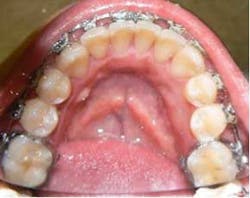

She came to me for an orthodontic consultation. She was 24 years old and hoping to marry her then-boyfriend at some point, but she didn't like her smile; she felt it was unattractive. So we gathered her orthodontic records and pointed out to her that it appeared she had either a supernumerary tooth or over-retained primary tooth between her upper centrals. Along with this, she also had some minor crowding on her lower teeth. She had a Class I molar relationship that I hoped to maintain.

Month 0-3 I like to start all my orthodontic cases off with a light round nickel titanium wire such as an 014N or 012N. While in this wire, I used some elastomeric chain to help align and rotate the teeth.Month 4-10 I continued to level the teeth and begin to reposition brackets on a 18X25 heat-activated NiTi wire based on a panoramic X-ray that I like to take to help me with root positioning.Month 11-16 Progress to a stainless steel 19x25 wire for more tooth torque and better bracket engagement.Month 16-18 Finishing on a 018SS. I don’t have much wire-bending skills, so I mostly move brackets and am capable of only some simple step bends.

Bleaching — We debanded the upper and performed a Zoom bleaching up top. At that time we also impressed to make a lower bonded lab-fabricated retainer. (I know we should do this in-office.)